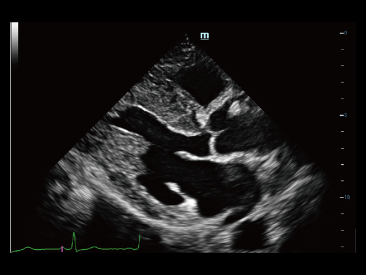

Fin dalla sua fondazione Mindray esplora continuamente nuovi modi per migliorare l'affidabilit├Ā diagnostica. Equipaggiata con la pi├╣ rivoluzionaria tecnologia ZONE Sonography?, la nuova piattaforma ZST+ di Resona 7 porta la qualit├Ā dell'immagine ecografica ad un livello superiore con l'acquisizione per zone e l'elaborazione dei dati canale.

Oltre alla qualit├Ā delle immagini di livello eccellente, Resona 7 migliora anche le capacit├Ā di ricerca clinica il rivoluzionario V Flow per la valutazione emodinamica vascolare, e l'acquisizione piani pi├╣ intelligente dal set di dati 3D per la diagnosi del sistema nervoso centrale fetale. Combinando il pi├╣ intuitivo funzionamento multi-touch basato su gesti e tutte le caratteristiche cliniche essenziali, Resona 7 sta veramente portando nuove tendenze nellŌĆÖinnovazione dellŌĆÖecografia.